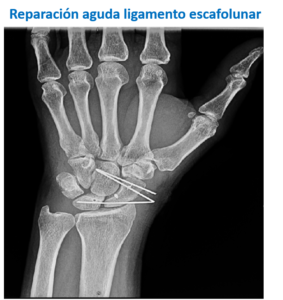

Raramente, en algunos esguinces grado III, estará indicado realizar una cirugía para colocar en posición adecuada los huesos y estabilizarlos temporalmente hasta que los ligamentos cicatricen. Esto sucede por ejemplo en algunas luxaciones del hueso semilunar o lesiones del ligamento escafolunar.

Las lesiones crónicas suelen requerir tratamiento mediante cirugía de forma más frecuente, sobre todo cuando son muy sintomáticas.